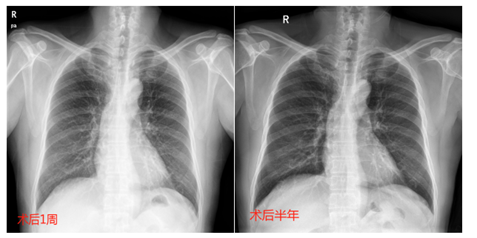

术后1-3天,予以半卧位APD治疗,单周期700-800ml,末次干腹;术后4-5天半卧位APD治疗,单周期1000ml,术后6-9天半卧位CAPD治疗,单周期1200ml,术后10-14天半卧位CAPD治疗,单周期1500ml(图3)。术后10天患者康复出院,继续居家行腹膜透析治疗,逐渐增加留腹量,规律随访未再出院胸腹瘘症状(图4)。